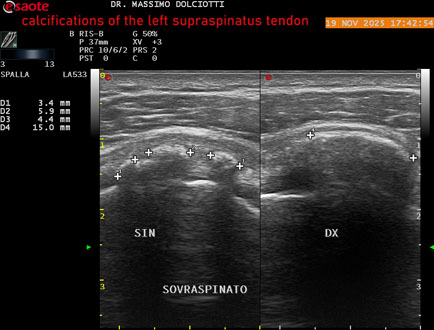

Ecografia del: 19/11/2025

Strumento: Esaote MyLab Eight

Sonda: Lineare Multifrequenza 3-13 MHz

Età Paziente: M 52 anni

Motivazione dell'esame: dolore alla spalla sinistra che peggiora con il freddo.

Commento all'esame: le immagini ed il video documentano il tendine sovraspinato sinistro disomogeneo per evidenza, in sede prossimale e mediale, di immagini iperecogene multiple, delle dimensioni di 5,8 mm - 6,1 mm - 4,6 mm da ricondurre a calcificazioni.

Conclusioni: calcificazioni del tendine sovraspinato sinistro (calcifications of the left supraspinatus tendon).

Presentazione: Dr. Massimo Dolciotti - Ancona

Elaborazione digitale: Andrea Dini - Ancona